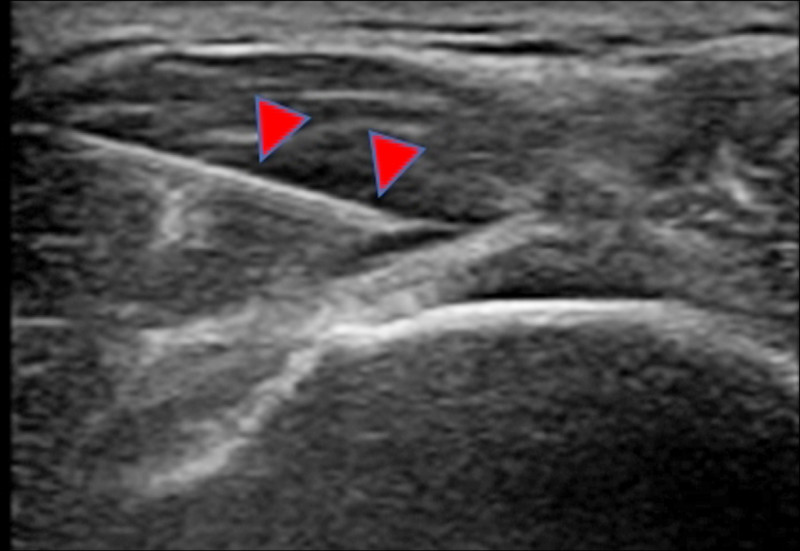

●進階的治療方式則包括高濃度葡萄糖增生療法(prolotherapy)以及高濃度自體血小板血漿(PRP)注射治療。兩者都是在超音波導引之下,將注射液打到肌腱撕裂的地方(圖2),讓受傷的組織進行修復。目前多個臨床醫學研究顯示療效不錯。